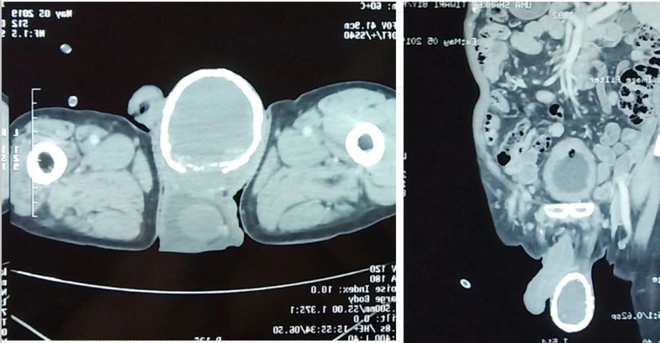

Ảnh chụp CT cho thấy một lớp vôi hóa như vỏ trứng bao quanh tinh hoàn phải của người đàn ông.

Ngay lập tức, họ đưa ông đi chụp cắt lớp CT, và phát hiện thấy một túi chứa dịch lỏng đang bao quanh tinh hoàn bên phải, mà lẽ ra nó không nên có mặt ở đó. Túi dịch lỏng này có một cái tên trong từ điển thuật ngữ y khoa. Các bác sĩ gọi nó là “hydrocele”, hay bao dịch tinh mạc.

Với sự xuất hiện của chiếc túi này, vô tình đã tạo ra một điều kiện tuyệt vời cho canxi lắng đọng và tạo nên một lớp vôi hóa dày như vỏ trứng xung quanh tinh hoàn của người đàn ông.

Nhiễm giun chỉ trong các hạch bạch huyết là nguyên nhân phổ biến nhất gây ra các bao dịch tinh mạc ở nam giới, theo các tác giả nghiên cứu trường hợp. Nhưng trường hợp tinh hoàn sau đó bị vôi hóa như người đàn ông Ấn Độ là một biến chứng cực kỳ hiếm gặp. Các bác sĩ cho rằng bao dịch tinh mạc của ông ấy đã phải nhiễm trùng rất lâu, thì mới có thể khiến canxi hình thành xung quanh nó.